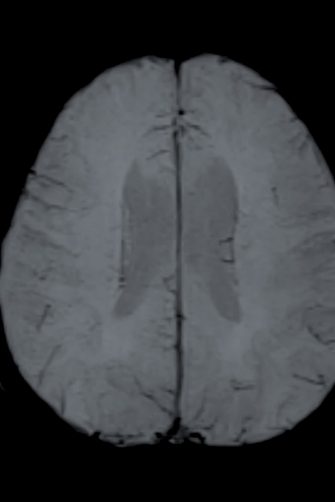

In this latest study, recently published in the journal Human Brain Mapping, Dr Haeme Park and Associate Professor Justine Gatt, who hold joint positions at UNSW Psychology and NeuRA, looked at how both emotion and cognition are influenced by the environment and genetics, using functional MRI (fMRI) scans on twins.

While the participants were completing the tasks, the fMRI machine was scanning their brain to measure its activity.

Processing the fMRI scans show you which part of the brain light up for different processes, and how strongly the brain is activated can be measured on a scale.